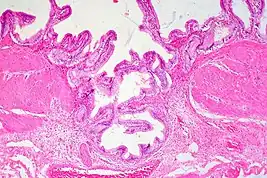

High magnification micrograph of uterine adenomyoma.

Uterine adenomyoma is the focal form of uterine adenomyosis. Adenomyosis most commonly presents with numerous small collections of endometrial glands and stroma spread diffusely throughout the myometrium, intermixed with the myometrial smooth muscle. In contrast, a uterine adenomyoma is an isolated nodular mass of endometrial tissue with surrounding smooth muscle, either embedded within the myometrium or extending from the endometrium into the uterine cavity in the form of a polyp.[2]